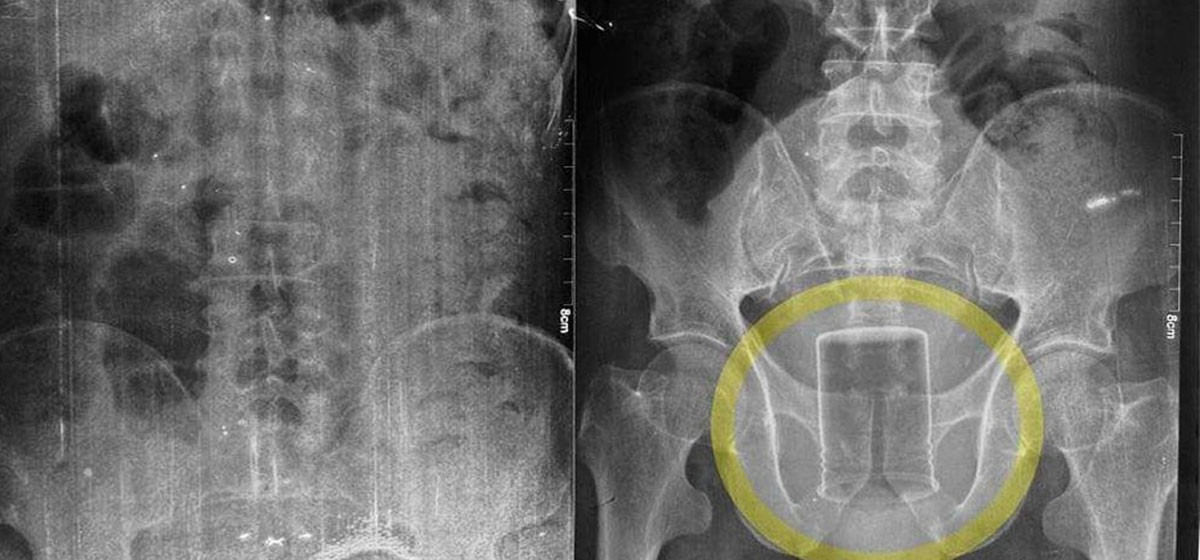

गोरखा, १० वैशाख : गोरखाका एक पुरुष आफ्नो स्वास्थ्यमा समस्या देखिएपछि आइतबार उपचारका लागि गोरखा अस्पतालको आकस्मिक कक्षमा पुगे । अस्पतालको आकस्मिक कक्षमा कार्यरत चिकित्सिकको टोलीले रोगको पहिचानका लागि परीक्षण गर्न सुरु गरे । उपचारका लागि आएका पुरुषको जाँचका क्रममा भिडियो एक्स–रे गरेर हेर्दा स्वास्थ्यकर्मी त्यतिबेला अचम्ममा परे जतिबेला उपचारका लागि आएका गोरखा नगरपालिका–३, नारेश्वरका ५७ वर्षीय ती पुरुषको मलद्वारमा धातुको बोतल अड्किएको देखियो ।

मलद्वारमा बोतल देखिएपछि चिकित्सकले सोधपुछ गर्दा एक महिनादेखि नै मलद्वारमा बोतल अड्किएको रहस्य खुल्यो । समस्याको पहिचान भएपछि बिरामीलाई तुरुन्तै अस्पतालको शल्यक्रिया कक्षमा राखेर दुरबिनबाट हेर्दा आन्द्राको अन्य भागमा सङ्क्रमण नफैलिएको पत्ता लागेपछि शल्यक्रिया गरेर ती पुरुषको मलद्वारमा अड्किएको धातुको बोतल निकालिएको गोरखा अस्पतालका सूचना अधिकारी लिपासा श्रेष्ठले राससलाई जानकारी दिनुभयो ।

“ती पुरुषको मलद्वारमा विगत एक महिनादेखि कीटनाशक औषधिको बोतल अड्किएको रहेछ”, उहाँले भन्नुभयो, “जब उपचारका लागि आइतबार बिहान १० बजे अस्पतालको आकस्मिक कक्षमा आएँ, त्यहाँ एक्स–रे गरेर हेर्दा मलद्वारमा बोतल देखिएपछि तत्काल शल्यक्रिया गरेर निकालिएको हो ।”

चिकित्सकले तीन घण्टा लगाएर गरिएको शल्यक्रियाबाट पुरुषको मलद्वारबाट १० सेन्टिमिटर लम्बाइ र ७.८ सेन्टिमिटर गोलाइको डब्बा निकालिएको हो । ती पुरुषको मलद्वारमा बोतल कसरी अड्कियो भन्नेबारेमा भने खुल्न बाँकी रहेको अस्पतालले जनाएको छ । शल्यक्रियापश्चात् बिरामीको अहिले अस्पतालको सघन उपचार कक्षमा राखेर उपचार भइरहेको सूचना अधिकारी श्रेष्ठले जानकारी दिनुभयो ।